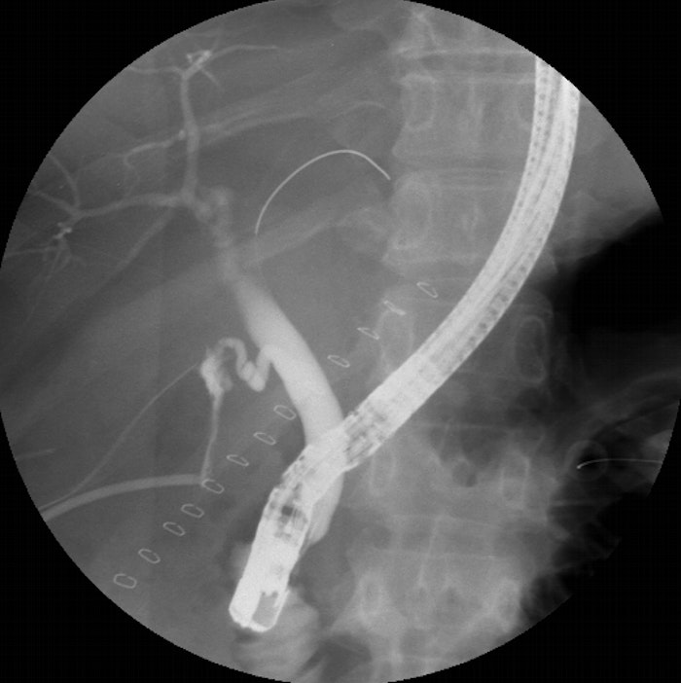

This middle-aged patient with diabetes mellitus underwent open cholecystectomy for an emphysematous gallbladder and presented 72-hours later with abdominal pain.

The most common recommendation is to perform a biliary sphincterotomy. Many experts also use a plastic stent alone or in combination with biliary sphincterotomy. Although it is commonly believed that placing a short-length stent is enough, we always take a good look at the type of leak, it’s size and location, and then decide on the length of the plastic stent. High volume leaks, or those associated with a big defect, tortuous bile duct or proximal location require a stent to be extending from proximal location, and extending across the papilla.

This means that in a bile leak scenario we have “bilio-athmospheric” (between the bile duct and outside world through the drain), the “bilio-abdominal or peritionel” (between the bile ducts and the intraabdominal cavity through the leak), and “bilio-enteric” (between the bile duct and the bowel through the ampulla) pressure gradients.The objective of a leak treatment will be for the bilioenteric gradient to be favored by “equalizing” the pressures between the biliary ductal system and the bowel, which is performed doing a sphincterotomy +/- stenting, as suggested by our colleagues in the discussion. This new gradient or “assistance to the bilioenteric drainage” would in theory be more favorable than the “bilioabdominal” gradient.However, another important point is to never forget the importance of the role the external drain plays. If this drain is still wide-open and immediately adjacent to the leak, the most favorable gradient for bile flow could still be the “bilio-athmospheric” one, even after sphincterotomy and possible stenting. Therefore, careful retraction of the drain a good 4-6cm from the site of the leak is recommended. This will theoretically now favor the bilioenteric route once again.